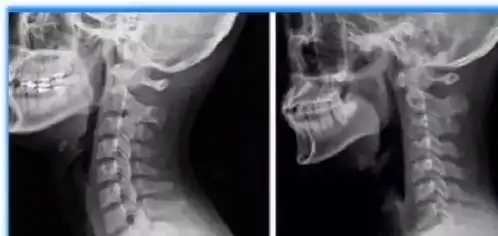

颈椎的日常防护